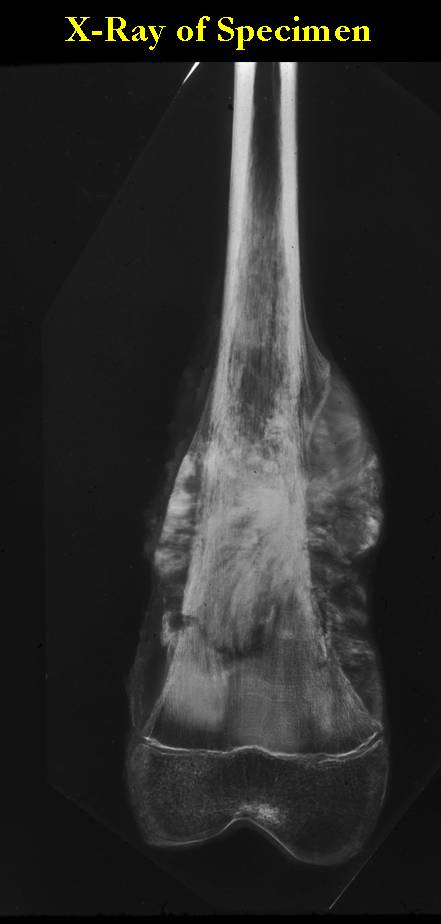

Gross Pathology: Conventional Osteosarcoma

These are examples of the gross pathology specimens of resected conventional osteosarcoma, consisting of both bony and soft tissue areas. X-rays of the specimens are included.

- Osteosarcomas are composed of ossified or non-ossified tissue

- Ossified tissue is yellow-white and hard

- Less ossified tissue is soft and less yellow

- Non-ossified tissue is tan and fleshy

- Most (95%) of conventional osteosarcomas penetrate the cortex and form a large extraosseous soft tissue mass

- The lesion permeates the marrow spaces

- Osteosarcomas usually infiltrate the marrow several centimeters away from the main tumor mass

- Skip lesions may be apparent that are separated from the main tumor by normal marrow

- Osteosarcomas may also have cartilaginous components that appear as translucent lobules, and/or fibrous components that are tan, soft to firm rubbery areas

- Osteoblastic areas are usually white to yellow, firm, hard and gritty

- The consistency of the tumor depends on the amount of osteoid deposition, cartilaginous and fibrous areas

- Foci of hemorrhage and necrosis are common

- Periosteal reactions such as the Codman’s triangle are apparent at periphery of soft tissue mass

- Osteosarcomas rarely penetrate the growth plate grossly

- Invasion of the joint is uncommon but can occur by cortical penetration, joint capsule extension, or extension along cruciate ligaments